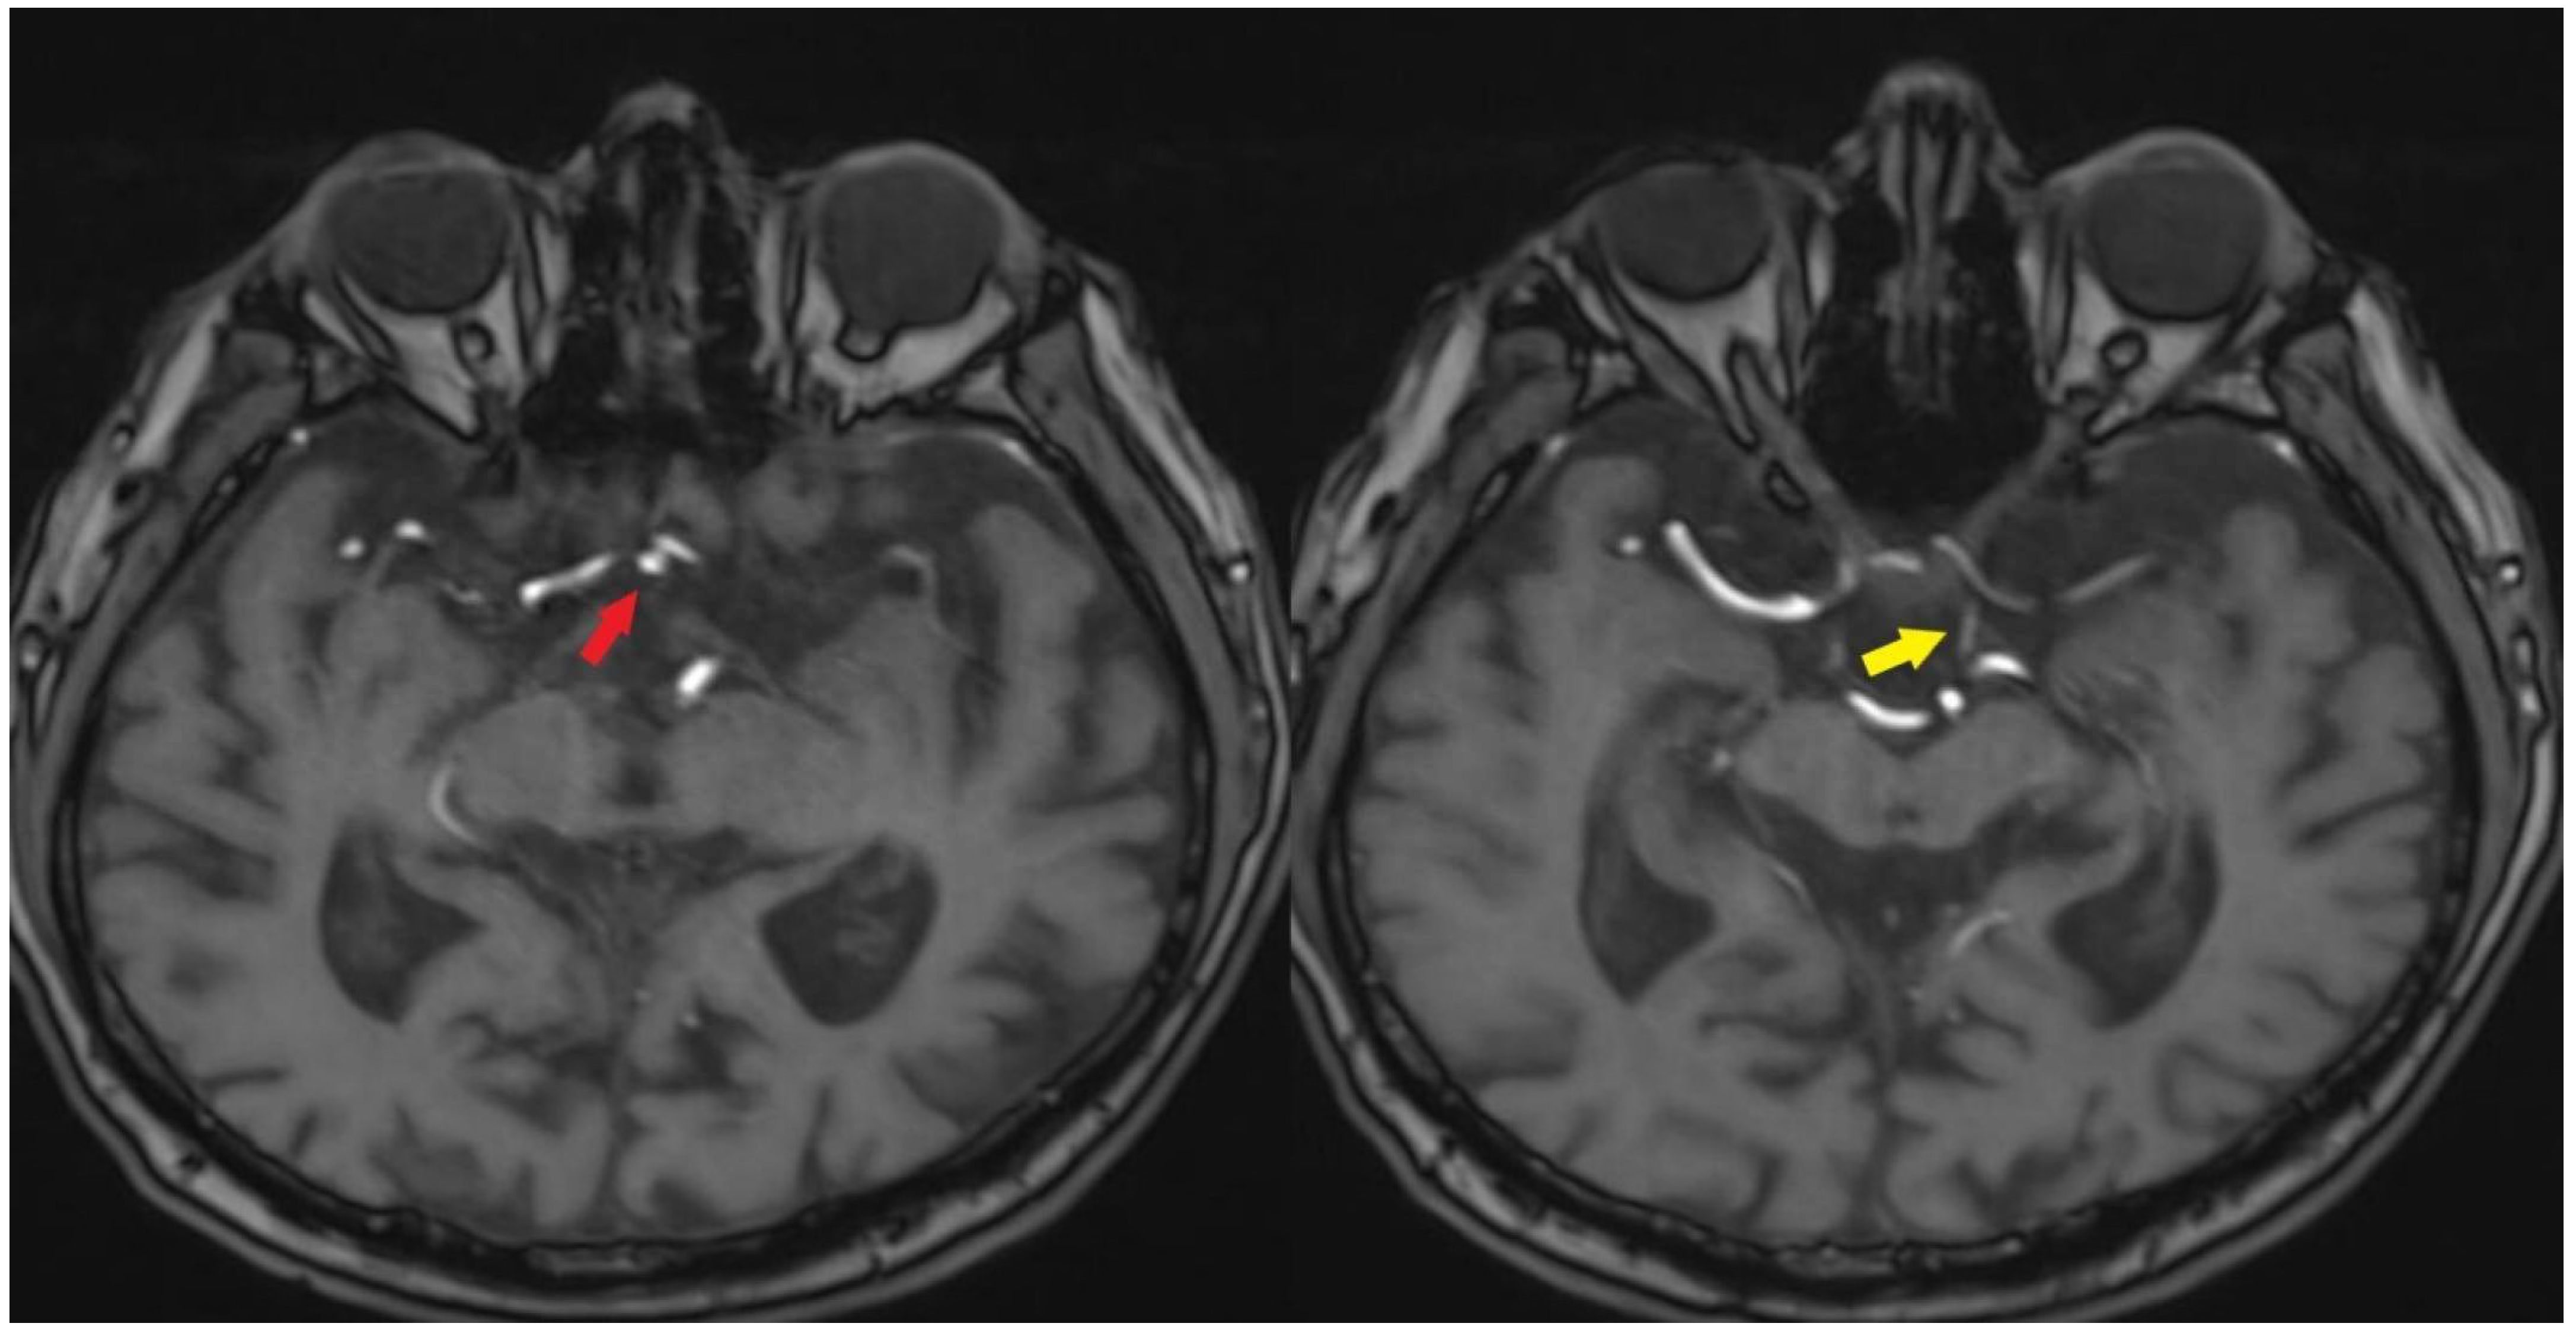

The anterior circulation has been supplied via the anterior communicating artery, while the posterior circulation has received perfusion through the posterior communicating artery (Figure 3).

Figure 3.

Anterior communicating artery [Red arrow] and posterior communicating artery [Yellow arrow], along with the vascular supply to the left hemisphere [TOF images].